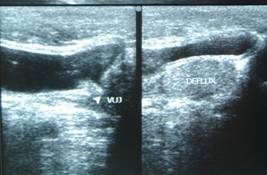

Torsion of Left Undescended Testis (Pre operative and Operative Photo)